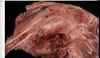

What is the etiology of a sheep with gun metal kidneys (black kidneys), widespread jaundice, normal liver, and red colored urine?

TEST QUESTION

Acute copper toxicosis

(sheep are insufficient in metallothionein for safe copper storage in the liver > chronic accumulation of copper in the liver > mild liver damage > acute copper release > oxidative RBC damage > intravascular hemolytic anemia > hemoglobinuria)